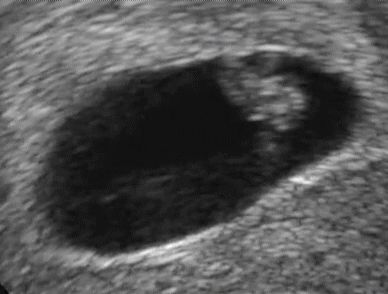

이렇게 쪼꼬만 심장이 뛰고있다니

6주 5일차에 심장소리 들었어요 첫 아이인데, 저렇게 작은 심장도 살아있다고 꼬물꼬물 심장이 뛰는게 너무 작고 소중하고 신기해요.. 괜히 눈물나.. ㅠㅠ